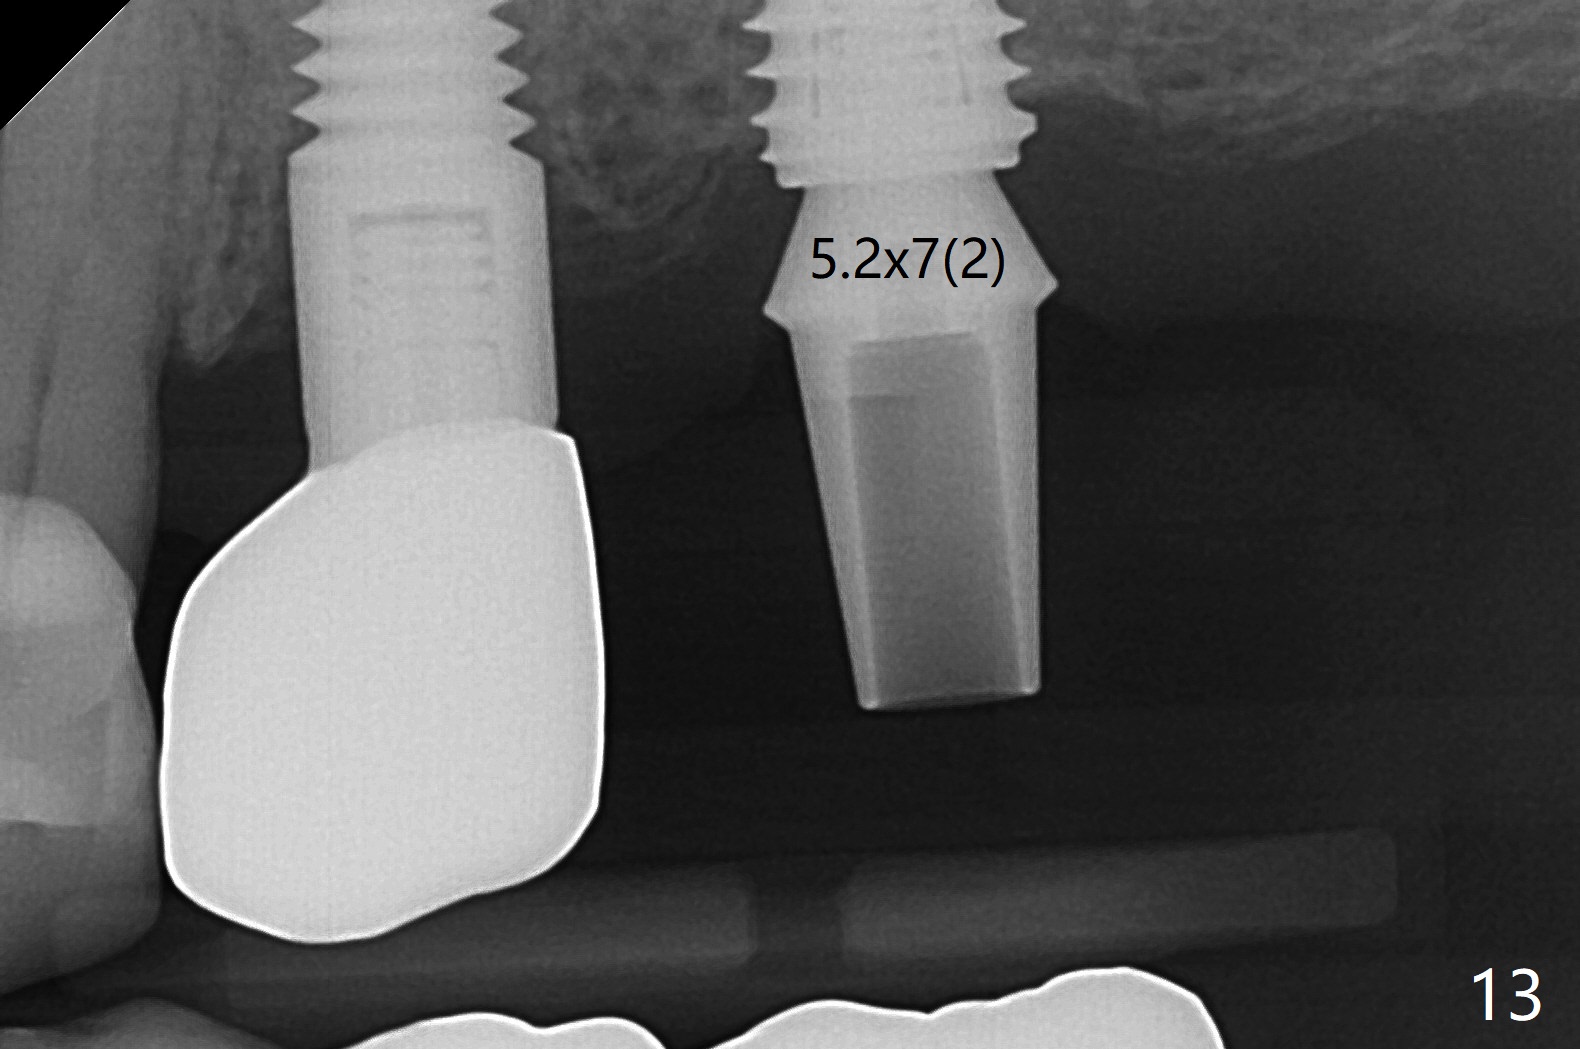

M

As a surgeon, I have never felt that my scalpel is as precise as media claims to be until guided surgery is introduced. The implants at #14 and 19 are placed as precisely as planned as well as painlessly and quickly (Fig.1-4). What else can we ask for? The gingiva around the healing abutment (5.5x3 mm) at #19 is erythematous (Fig.5). Later a longer healing abutment is used (Fig.6 (5.5x5 mm)). There is no bone loss 5 months or 7 months postop (Fig.6-9). The abutment screw is loose 3 months post cementation due to unfavorable crown/implant ratio (Fig.10); in fact the abutment is incompletely seated. Bicon implants will be in consideration to reduce screw loosening if implants are to be placed at #15 and 18. The abutment screw at #14 becomes loose 10 months post cementation; after retorque at #30 Ncm, the abutment is incompletely seated (Fig.11). It remains the same after use of 4.6 and 5.6 mm profile drills (Fig.12). A healing abutment is placed. When the patient returns, use planning kit and try to place a 5.2x5.5(2) cemented abutment. In fact it works (Fig.13). The crown at #19 is loose again 1 year 5 months post retightening. After removing crown/abutment, the mesial surface of the crown is heavily reduced. The crown/abutment is reseated to make sure that there is no proximal contact between the neighboring teeth (Fig.14 arrow). Because of tilt of the PA, it is difficult to tell the tightness of the contact between the implant and abutment, but the apical space is significantly reduced (*, as compared to Fig.10). Pick up impression is taken for porcelain addition occlusomesially. Two months later the patient returns for crown recementation. When the abutment is reseated with the repaired crown, the seating is incomplete (Fig.15). The abutment is completely seated when it is turned free hand with the flat surface of the abutment faces distal (Fig.16 D). The screw is torqued 20 Ncm before reimpression.